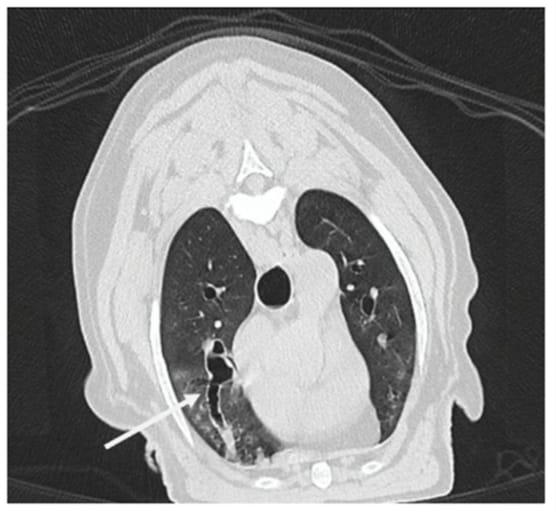

Transverse computed tomography image (lung window) in expiratory phase of a dog with severe bronchiectasis. Presence of an irregular dilation in longitudinal section of the stem bronchus of the right cranial lung lobe (white arrow). This dilation is associated with bronchial wall thickening along the entire length and takes on a saccular appearance toward the periphery. A heterogeneous increase in lung parenchymal attenuation is also present, taking on a ground-glass opacification.